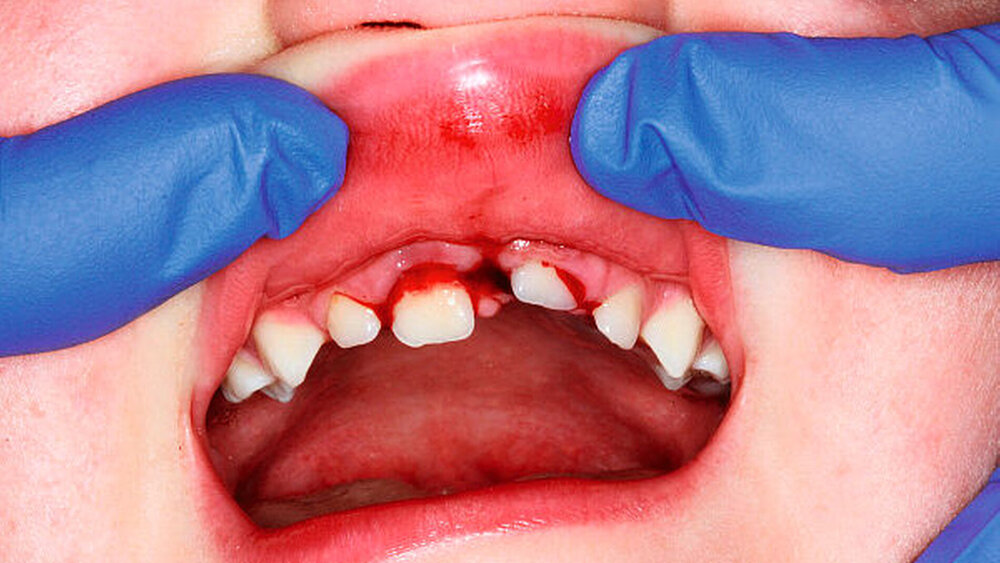

Im Fall der Intrusionsverletzung des Zahnes 21 bei einem siebenjährigen Kind (Abbildung 1) würde im Rahmen der Weichteilversorgung die chirurgische Reposition als sofortige Dekompressionsmaßnahme des Zahnes 21 gleich mit durchgeführt werden. Denn im Rahmen der Sofortversorgung lässt sich der Zahn 21 leicht mit der Zange fassen und wieder in Okklusionsposition einstellen – gefolgt von flexibler Schienung für zehn Tage. Alternativ steht die schrittweise kieferorthopädische Extrusion zur Verfügung. Eine Schädigung des Zahnkeims ist bereits durch die Art des Zahntraumas zu erwarten. Mit erhöhter Wahrscheinlichkeit handelt es sich dabei um eine Ankylose des Zahnes mit zusätzlicher vertikaler Wachstumshemmung.